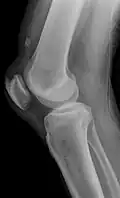

Kompletter Riss mit tief stehender Patella -